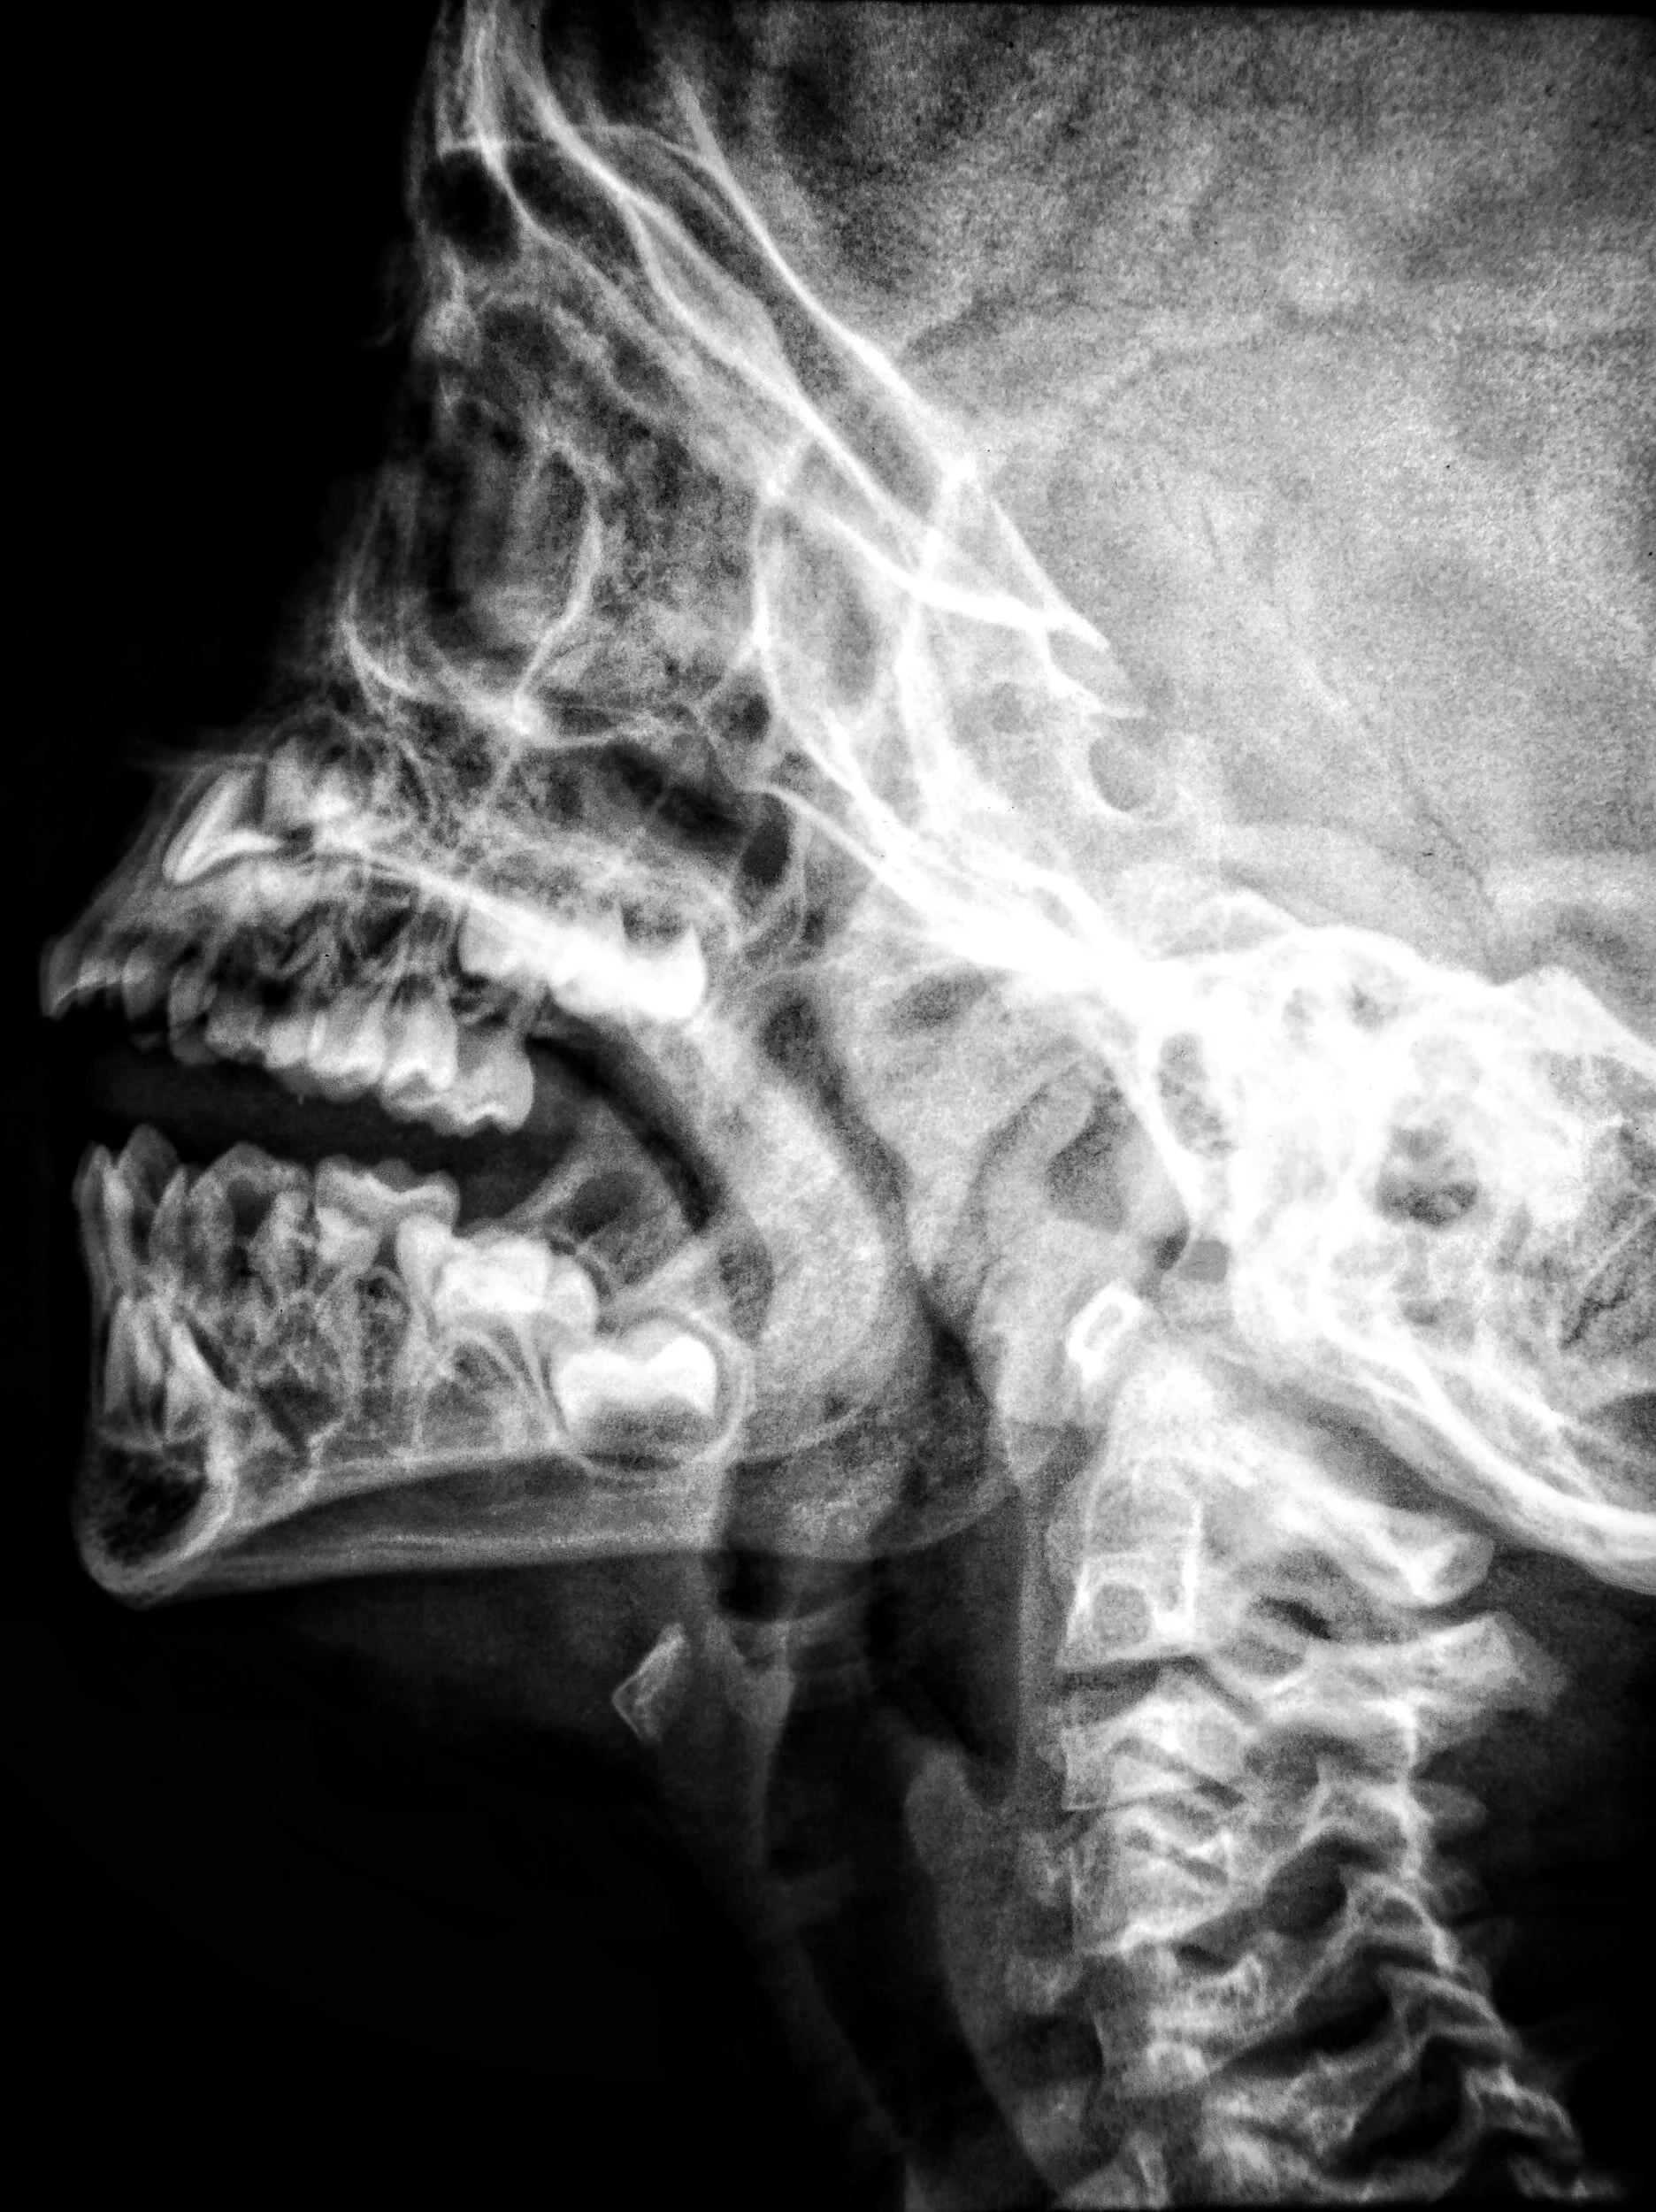

Do I need X-rays or an MRI?

In most cases, no. Research has consistently pointed out that imaging for neck pain does not increase the safety or effectiveness of treatment unless certain factors are present. If we suspect a fracture or disc injury then imaging could be useful, but for most people this is not the case.